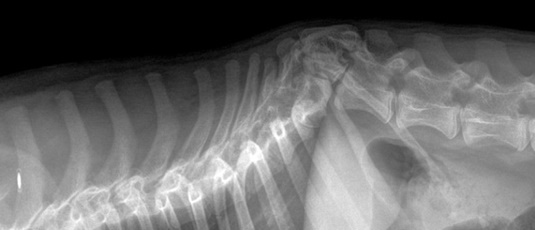

Πλάγιο ακτινογράφημα ΣΣ. Ο Θ13 είναι ραχιαίος ημισπόνδυλος ή σφηνοειδής σπόνδυλος με την κορυφή κοιλιακά.